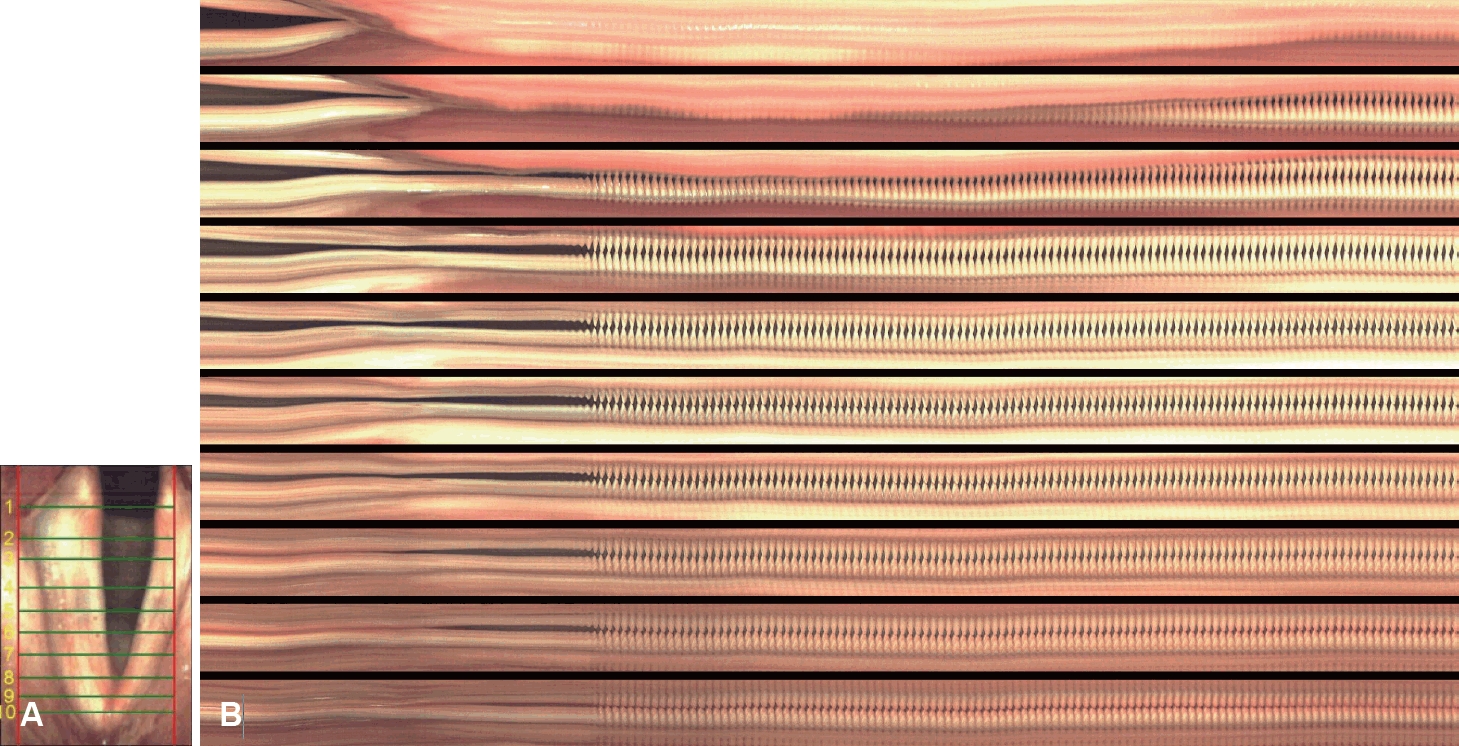

503 Quiz

Korean J Otorhinolaryngol-Head Neck Surg. 2025;68(11):503-503.   Published online November 25, 2025